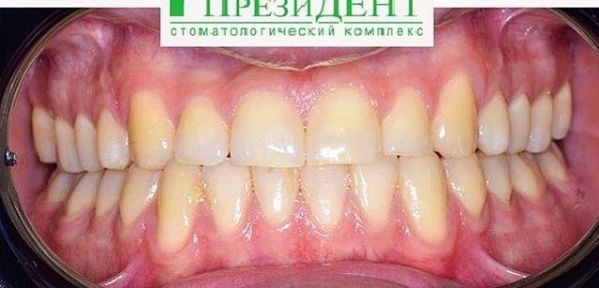

4 работы в портфолио

Врач Заводова (Рыбась) Анна Викторовна принимает в стоматологическом комплексе ПРЕЗИДЕНТ НА ЛЮБЛИНСКОЙ в Москве. Имеет рабочий стаж 21 год. Специализируется на ортодонтии, по которой клиника оказывает 3 услуги. Имеет 4 работы до/после в портфолио. Квалификация специалиста подтверждена 15 лицензиями, сертификатами и наградами. Для уточнения дополнительной информации о специалисте или записи на прием можно позвонить по телефону